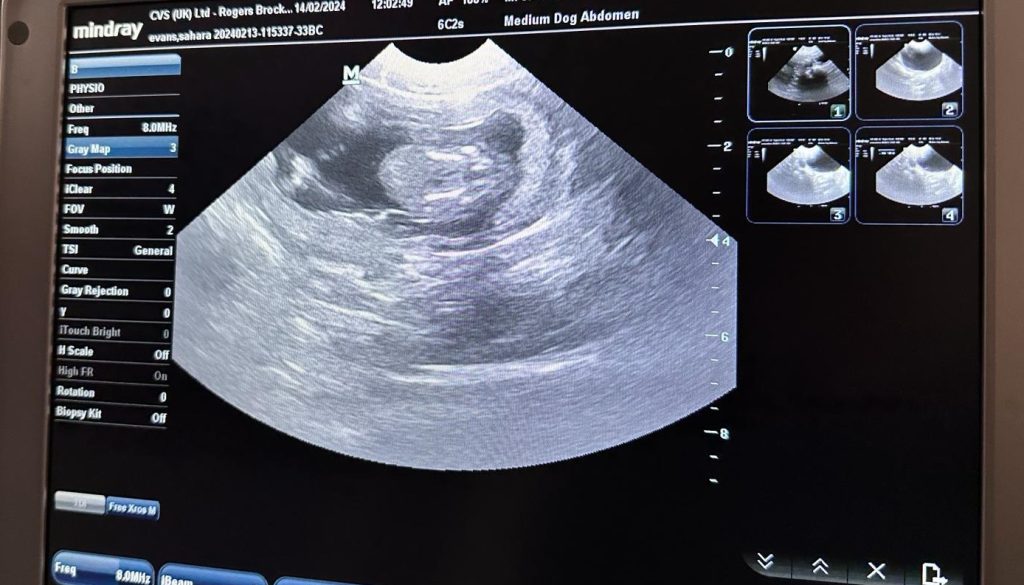

Trentham Monkey Forest has successfully carried out its first-ever ultrasound examination on a monkey called ‘Pretty’ and discovered that she is in fact, PREGNANT!

The video of the scan shows Pretty’s adorable bundle nestled safely within her womb and confirms her to be the first monkey mum of the season for Monkey Forest.

Whilst there, the team was desperate to see whether she was again, an expecting monkey mum, so asked for the ultrasound scan to be performed and were over the moon to see a beautiful bundle appear!

The team are thrilled to hear about Pretty’s healthy growing baby as usually, the first they hear or see of baby news is when a monkey mum carries her new-born bundle down from the trees in the morning when feeding the monkeys breakfast.